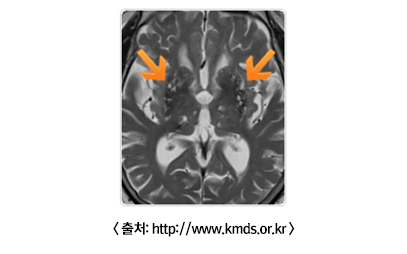

MRI 검사

• - 파킨슨병의 경우에는 MRI가 정상소견인 반면에 다른 질환들은 특징적인 MRI 소견을 보입니다.

• 2) 혈관성 파킨슨 증후군 : 뇌졸중 위험인자(고혈압, 당뇨, 고지혈증, 담배, 술 등)를 가진 경우에, 뇌 안에서 무증상 뇌경색들이 생길 수 있습니다. 혈관이 막힘으로써 뇌손상이 발생하는 것을 뇌경색이라고 합니다. 큰 혈관이 막히는 경우와 달리, 작은 뇌혈관은 한 번 막혔을 때 손상되는 뇌세포가 적어, 무증상으로 있는 경우가 많으므로 무증상 뇌경색이라고 부릅니다. 그러나 이러한 무증상 뇌경색들이 반복해서 많이 생길 경우(화살표: 왼쪽, 오른쪽 뇌 모두 무증상 뇌경색들이 많음을 볼 수 있습니다.) 보행장애, 치매 등의 증상을 보일 수 있습니다.